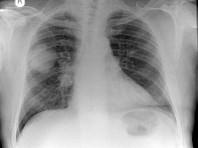

问题 男,58岁,咳嗽、气促3个月,抽烟二十余年,请结合胸片选择最可能的诊断()

选项 A.肺癌 B.胸膜间皮瘤 C.肺结核 D.错构瘤 E.结节病

答案 A